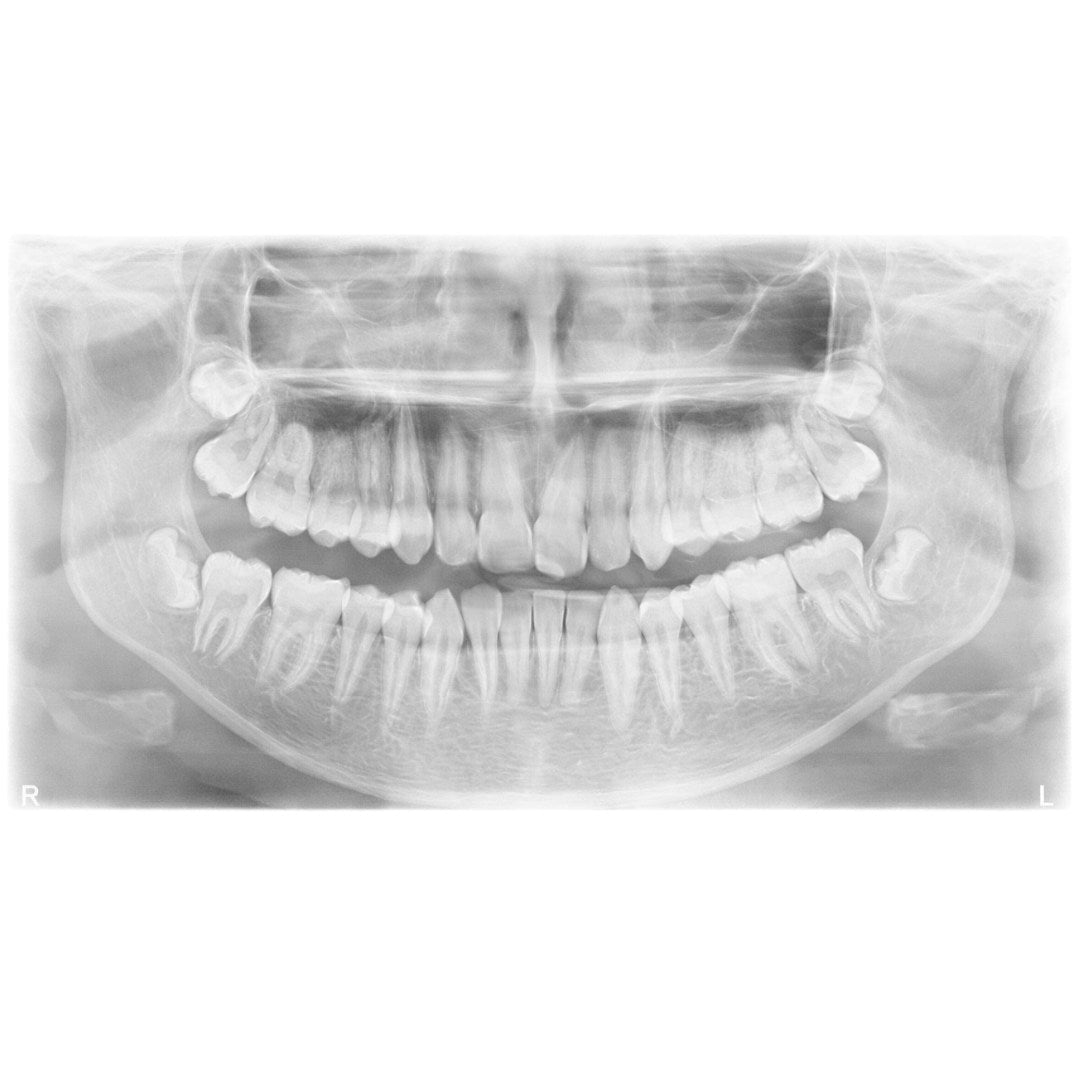

Røntgenbilder er et viktig diagnostisk verktøy i moderne tannhelse. Hos Clinica MedSpa benytter vi avansert røntgenteknologi for å få detaljerte bilder av tennene, kjeven og omkringliggende strukturer. Dette gjør det mulig for tannlegen å oppdage skjulte problemer som ikke kan sees med det blotte øye, som karies i tennene, infeksjoner under tannkjøttet, eller problemer med kjeven. Røntgenbilder gir oss en grundig innsikt i tannhelsen din, som kan bidra til tidlig påvisning av problemer og mer presis behandling.

Vi benytter digitale røntgenbilder, som gir høy oppløsning og umiddelbare resultater, samtidig som det er mer skånsomt for pasientens helse sammenlignet med tradisjonelle røntgenmetoder.

Digitale røntgenbilder er essensielt for presis diagnostikk og effektiv behandling. Vi bruker moderne røntgenteknologi som gir svært detaljerte bilder av tenner, tannrøtter, kjeveben og omliggende strukturer. Dette gjør at tannlegen raskt og nøyaktig kan identifisere problemer som karies, betennelser, infeksjoner og andre skjulte tilstander.